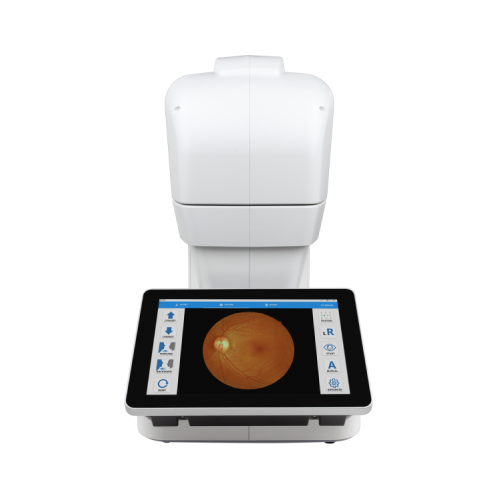

Інфрачервона Фундус Камера NFC-700 Crystalvue

Немідріатична фундус-камера NFC-700 Crystalvue є автоматичною системою тривимірного відстеження, швидкого і простого у використанні, відображення сітківки ока. NFC-700 призначена для отримання зображень ока для діагностики діабетичної ретинопатії, ВДМ, глаукоми та інших захворювань сітківки.

NFC-700 забезпечує зображення немідріатичного кольору сітківки ока і зовнішніх зображень ока як допоміжний засіб для лікарів при оцінці та діагностиці захворювань очей.

Автоматична фундус камера NFC-700 використовує БІЧ-світлодіоди в якості підсвічування при вирівнюванні сітківки ока пацієнта, вона забезпечує тільки зйомку зображень і жодним чином не надає жодних діагностичних або патологічних аналізів або висновків. NFC-700 також не призначена для використання в якості єдиного діагностичного засобу виявлення, класифікації або лікування захворювань.

Великий сенсорний екран 10,1 дюйма

Сенсорною панеллю легко керувати. Деталі зображення можна побачити та перевірити більш детально та точно через великий екран.